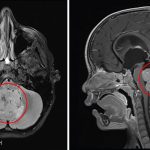

Si chiama GENE RAI 1 (Retinoic Acid Induced 1) e ha un ruolo fondamentale nello sviluppo dell’embrione. Il suo malfunzionamento può causare malattie a oggi incurabili, ma anche disordini del neurosviluppo infantile. Alla “disregolazione” di questo gene-chiave vanno infatti ricondotte malattie rare quali Smith-Magenis o Potocki Lupski, così come vari disturbi nell’apprendimento, nel movimento, nel linguaggio che colpiscono tanti bambini nei primi anni di vita.

Obiettivo della ricerca è comprendere perché i bambini con mutazioni del Gene RAI1 manifestino precocemente sintomi di disturbi cognitivi e motori, ma anche gravi disordini dell’alimentazione e del sonno. Alla de-regolazione dei geni che controllano il ciclo circadiano (l’orologio biologico che presidia l’arco delle 24 ore) va ricondotto, per esempio, uno dei maggiori problemi per questi piccoli che tendono a fare molteplici sonnellini durante il giorno e, invece, a stare svegli durante la notte. Si aggiunga che, a oggi, non esistono terapie farmacologiche efficaci per fronteggiare le sindromi legate a questo gene (le terapie comportamentali sono, al momento, l’unica modalità di intervento) o per formulare diagnosi precoci.

Cellule in laboratorio per una ricerca “geniale” – I laboratori di biologia molecolare e cellulare impegnati nella ricerca offrono competenze professionali e scientifiche di altissimo livello e sono dotati delle strumentazioni indispensabili per produrre in laboratorio le cellule staminali neurali. Infatti una piccola quantità di tessuto cutaneo tratto da un paziente affetto da malattia rara consente di coltivare le cellule in laboratorio. Messe a confronto con cellule di donatori sani, quelle “riprogrammate” evidenziano i problemi legati alla mutazione genetica. L’obiettivo è, pertanto, quello di sviluppare modelli che favoriscano lo studio delle malattie attraverso tecniche di riprogrammazione cellulare, lavorando sulle biopsie cutanee di pazienti malati.

Lo conferma la dottoressa Jessica Rosati, coordinatore dell’Unità di Riprogrammazione cellulare dell’Istituto Casa di Sollievo della Sofferenza – Mendel di Roma: “Proprio questa struttura è stata la prima a realizzare in laboratorio cellule staminali neurali, partendo da cellule prelevate dall’epidermide di una paziente affetta dalla sindrome Smith-Magenis. Grazie a questa sofisticata tecnologia, è stato possibile superare le difficoltà intrinsecamente legate alle ricerche sul cervello in via di sviluppo e verificare come la singola mutazione del gene RAI 1 produca molteplici effetti all’interno della cellula stessa”.